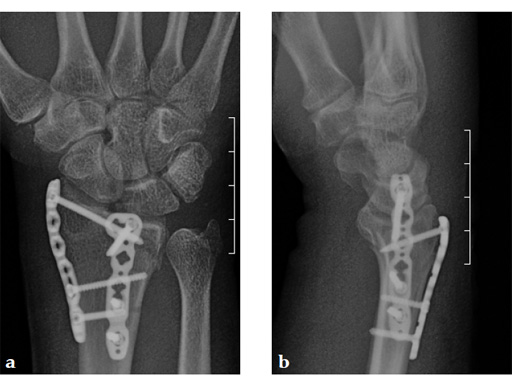

Case 2: A 44-year-old man sustained polytrauma following a car accident. Among his injuries was a distal radial fracture, Mller AO Classification 23-C1.

Case provided by Vitezslav Ruber, Brno, Czech Republic